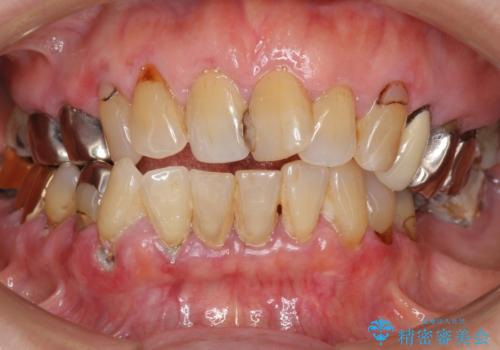

ぷくっと腫れた歯肉が気になる 根管治療とセラミック

- 奥歯の裏側の歯肉が腫れていることを主訴にご来院された患者様です。古いつめものの下が虫歯になり、細菌が増殖して膿がたまっていることが原因でした。

根管治療とオールセラミッククラウン(スタンダード)での治療をご希望されました。

ご来院当初は、歯肉が腫れていることにより、患者様ご本人は歯周病を心配されていました。しかし、診査した結果、歯周病はなく、歯肉が腫れている原因は虫歯(大きくなった虫歯により根管が細菌で汚染されていた)でした。4回にわけて根管治療をさせて頂きましたが、その都度歯肉の腫れが小さくなっていくのを実感して頂きました。

今回のように、大きい虫歯を長期放置していると、痛みがなくても歯肉が腫れてくることがあります。

歯肉がきれいに治り、患者様には大変満足して頂きました。